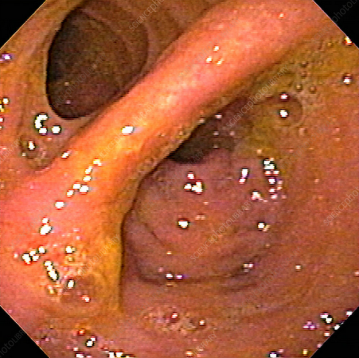

Κολονοσκόπηση. Ευδιάκριτα ευρήματα ισχαιμικής κολίτιδας (Ευγενική παραχώρηση Dr. V. Penopoulos)

Λεπτομέρεια των εκτεταμένων βλαβών στο εγκάρσιο κόλον (Ευγενική παραχώρηση Dr. V. Penopoulos)